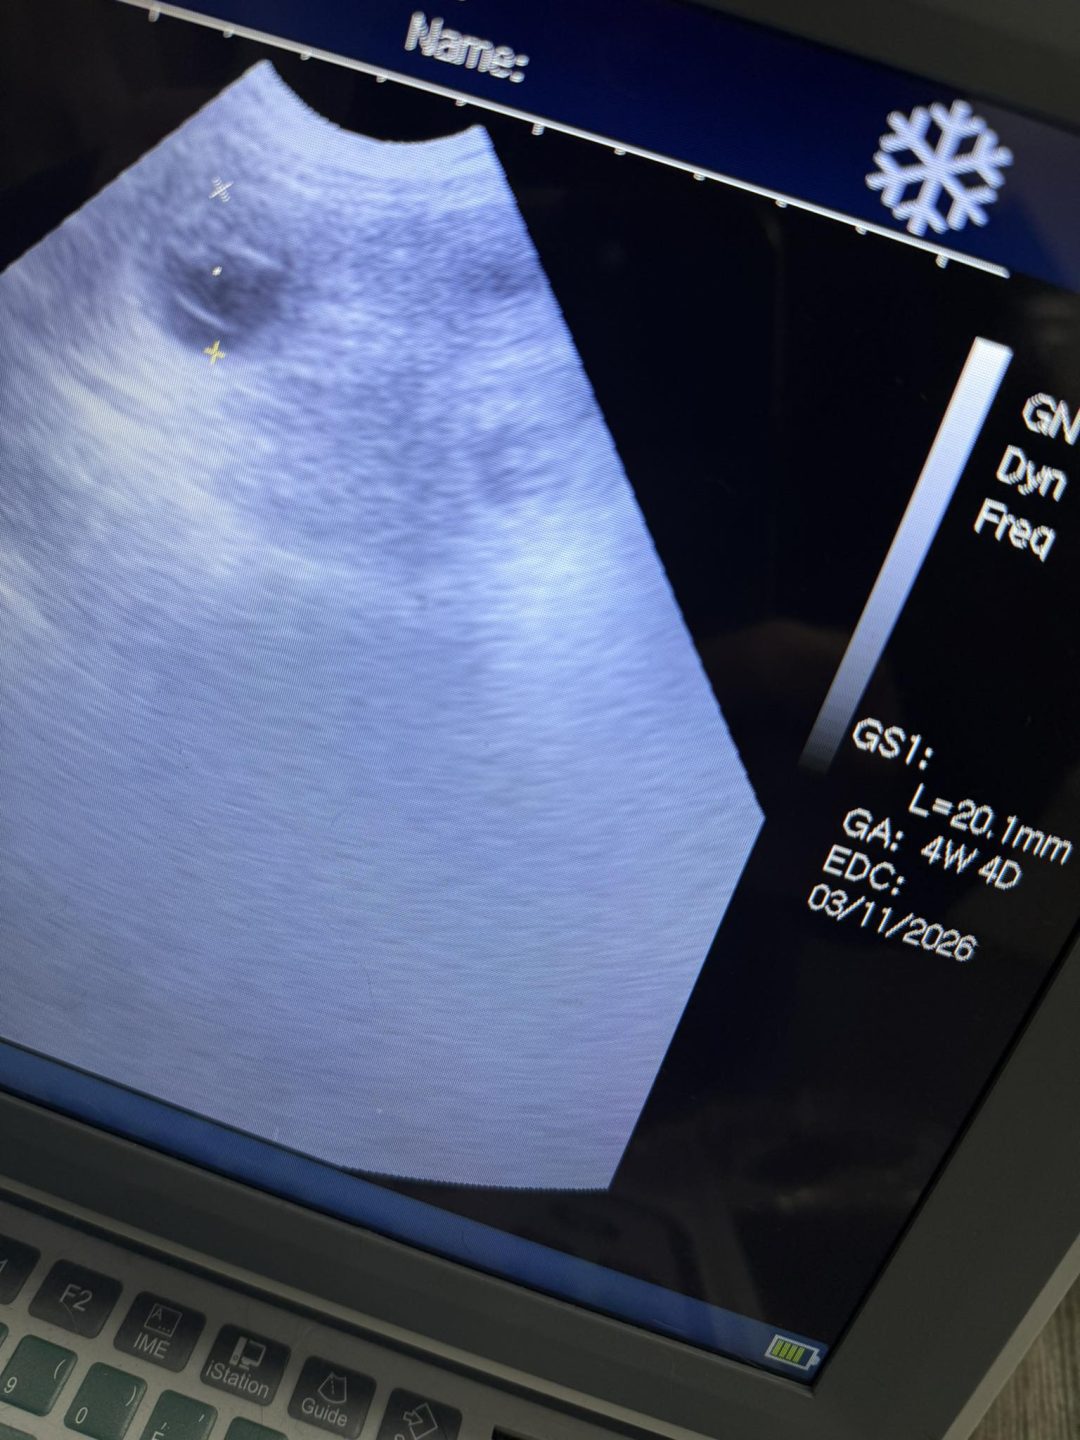

Confirmation ultrasound scan carried out here at Preston’s K9 fertility services this morning

I were happy to announce this girl in pup with a belly full of babies

Estimated due date and puppy count given

I carried out this girl’s progesterone bloods and cytology swabs before she visited her owners choosen stud boy, to make sure they met up at the correct timing